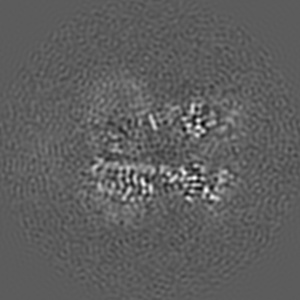

Cyro-EM structure of human Glycine Receptor alpha2-beta heteromer, glycine bound, (semi)open state

Sample: Glycine receptor alpha2-beta heteromer, glycine bound, open state

Characterization of the subunit composition and structure of adult human glycine receptors

Yu H, Bai X-C, Wang W

(2021) Neuron , 109 , 2707 - 2716